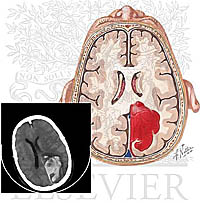

Đa chấm xuất huyết và khối máu tụ trong não liên quan SLGL lạc chỗ trong não và mắt

Liangxue Zhou, MD thuộc khoa phẩu thuật thần kinh, West China Hospital, Sichuan University, Chengdu, 610041 China và Lingli Luo, thuộc khoa gây mê hồi sức, West China Hospital, Sichuan University, Chengdu, 610041 China; Chao You, thuộc khoa phẩu thuật thần kinh, West China Hospital, Sichuan University, Chengdu, 610041 China; Bing Wang, khoa phẩu thuật thần kinh, West China Hospital, Sichuan University, Chengdu, 610041 China; Jianguo Xu, Lin Liao, thuộc khoa ký sinh trùng, West China Center of Medical Science, Sichuan University, Chengdu, China; Xuhui Hui, khoa phẩu thuật thần kinh, West China Hospital, Sichuan University, Chengdu, 610041 China; Bowen Cai, khoa phẩu thuật thần kinh, West China Hospital, Sichuan University, Chengdu, 610041 China cùng nghiên cứu cho kết quả:

Sán lá gan lớn là một bệnh nhiễm trùng ký sinh trùng do loài Fasciola hepatica. Người nhiễm phải do tình cờ do ăn phải thực phẩm nhiễm ấu trùng giai đoạn nhiễm metacercariae; ký sinh trùng tồn tại hầu như trong đường mật nhưng hiếm khi thấy ở các cơ quan khác. Chúng tôi báo cáo một ca bệnh lạc chỗ thú vị trên cả não và mắt (P) của một cậu bé đang tuổi đi học, điều này có liên quan đến hai khối phình mạch chưa vỡ. Đối với những gì chúng tôi hiểu biểu, chưa có ca nào tìm thấy trên y văn tương tự.

Sau khi tiêu hóa loại cua sống Potamon denticulata trong vòng 4 tháng, một câu bé 10 tuổi cho thấy các đặc điểm lâm sàng trên hệ thần kinh gây ra bởi 5 giai đoạn của xuất huyết trong sọ não và khối máu tụ. Đồng thời, cậu bé bị đau rất dữ ở mắt (P) kèm theo đau đầu, nôn mửa, đau nhức mắt và lồi mắt, liệt dây thần kinh mắt số 6. Chụp X quang kỹ thuật số cho thấy có hai khối phình mạch chưa vỡ trong não. Chẩn đoán xác định ca bênh này xác định nhờ vào quan sát thấy giun di chuyển ra khỏi vết phồng vùng kết mạc của bệnh nhân và nhờ vào kết quả xét nghiệm cận lâm sàng. Bệnh nhân được điều trị bằng praziquantel và các triệu chứng hồi phục. Hai khối phình mạch không được phẩu thuật nhưng lại phải theo dõi lâu dài. Theo dõi trên phim chụp DSA cho thấy một khối phình mạch biến mất nhưng khối còn lại vẫn giũ nguyên.

Đa khối xuất huyết ở não và khối máu tụ có thể có liên quan đến bệnh lý sán lá gan lớn lạc chỗ trong não và mắt. Nhiễm trùng nội sọ đôi khi gây ra do sán F. hepatica hoặc các loài ký sinh trùng khác có thể dẫn đến sốt không rõ nguyên nhân, tăng bạch cầu ái toan và xuất huyết nội sọ không rõ nguồn căn. Việc tiêu hóa phải các loài cua sống P. denticulata có thể là một đường lan truyền không thường xuyên của bệnh sán lá gan lớn.